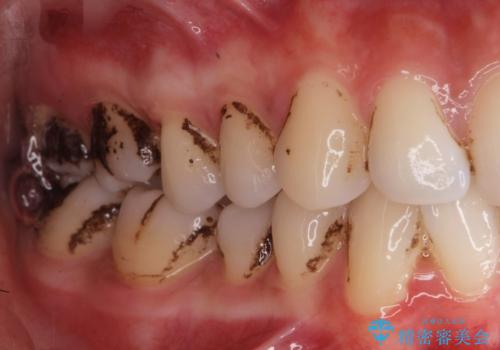

着色が気になる(エアフロー)

- 着色が気になるとの事で来院。

エアフローでしっかり着色を取り除きました。

着色が目立たなくなり大変満足して頂けました。